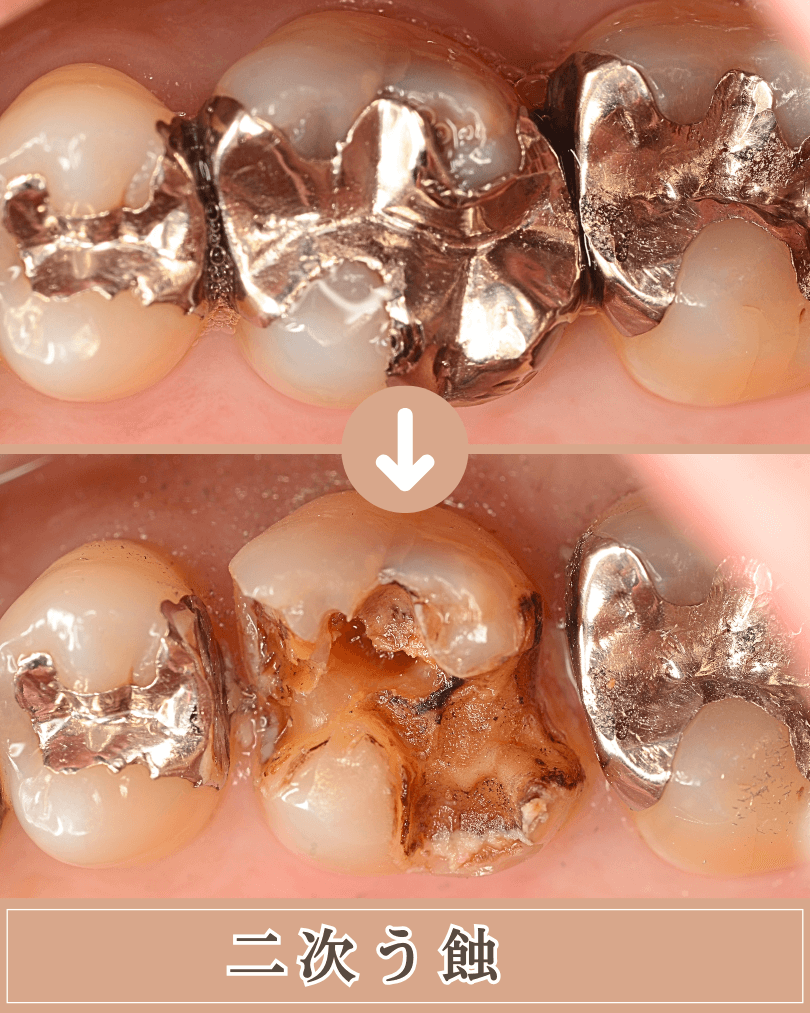

つめもの、さし歯のまわりや内部(二次う蝕)

過去に治療した歯のつめ物やさし歯の周囲・内部も虫歯になりやすい場所です。

二次う蝕・再発虫歯とも呼ばれます。

原因として、 歯とつめものやさし歯の境目には、時間が経つにつれて小さなすき間が生じ、そこに細菌が入り込むことで、再び虫歯が始まります。

また、つめ物やさし歯を固定している接着剤は、唾液や時間の影響で少しずつ劣化し、細菌の侵入口になることがあります。

これらは、精密なつめものやさし歯を製作すること、治療後の定期的なメンテナンス受診を続ける事で、抑える事ができます。

インレー治療後の二次う蝕(ブログ) コンポジット・レジン下の二次う蝕(ブログ)